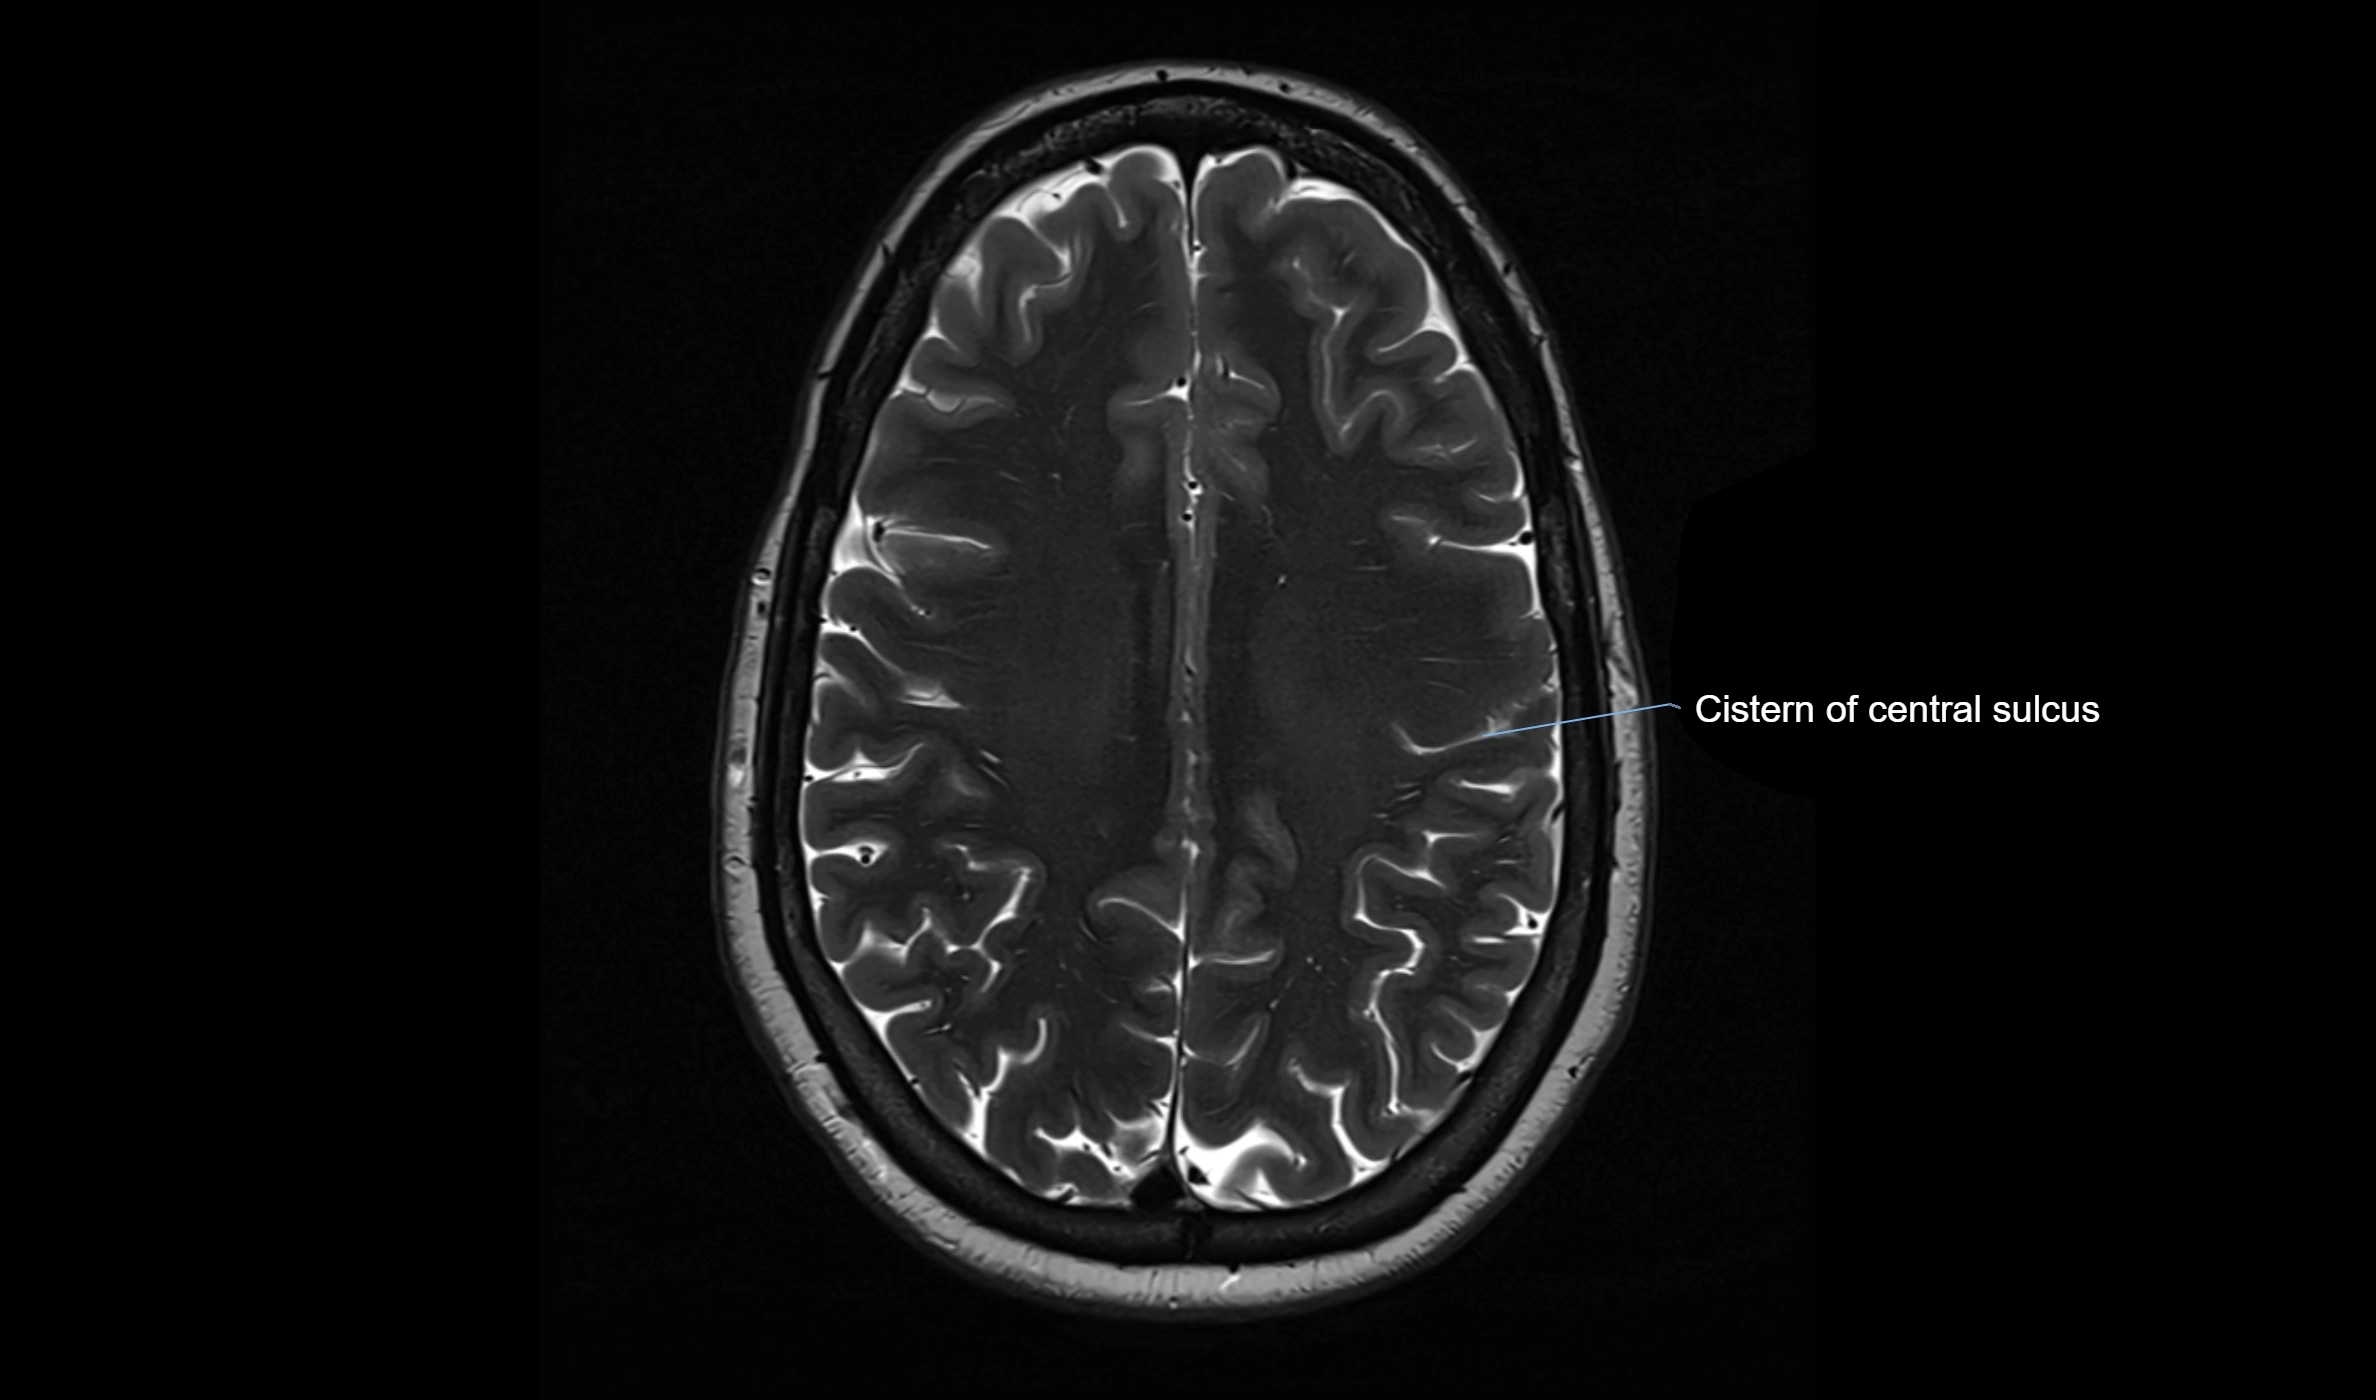

CT image

image